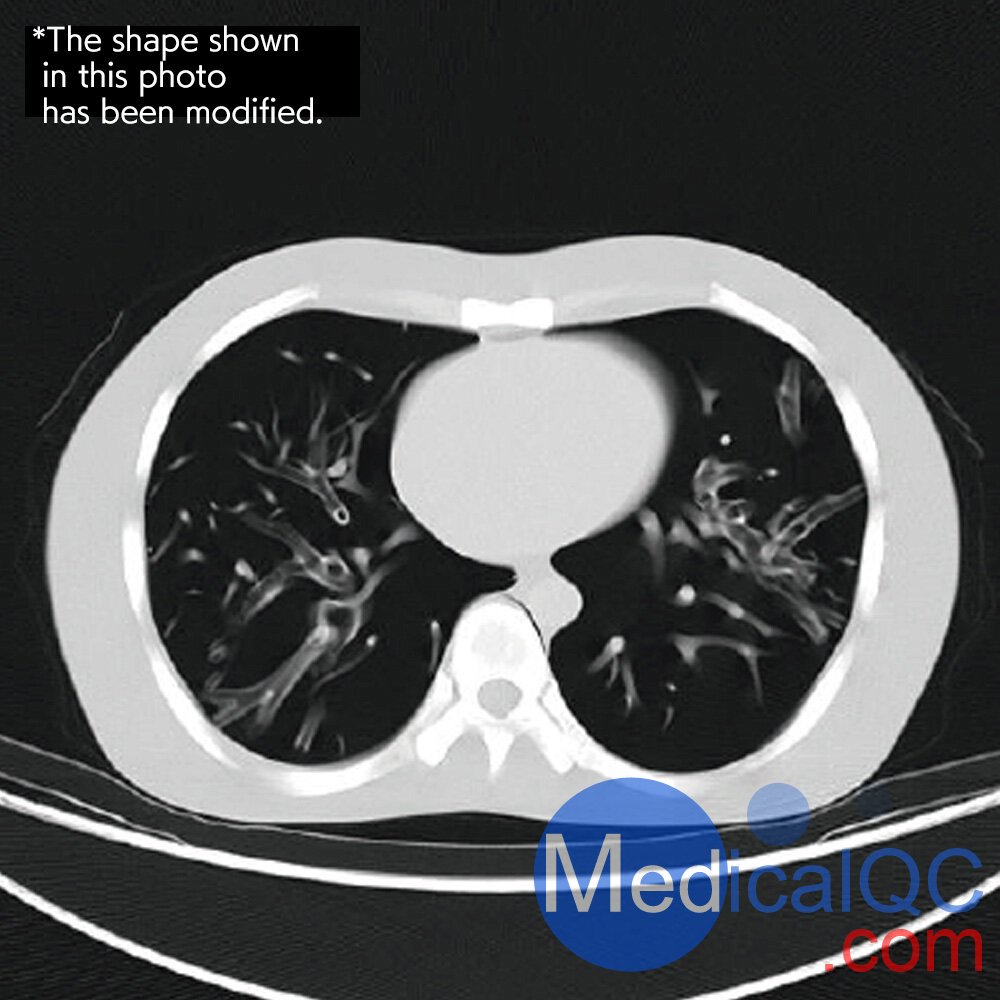

CTU-41 CT躯干模体,PH-4 CT躯干模型,CT人体躯干模型PH-4成像效果:

CTU-41 CT躯干模体,PH-4 CT躯干模型,CT人体躯干模型PH-4成像效果  CTU-41 CT躯干模体,PH-4 CT躯干模型,CT人体躯干模型PH-4成像效果